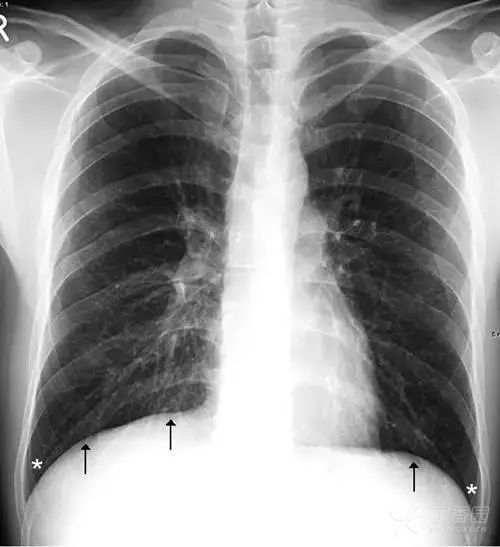

横膈分隔胸、腹腔,呈圆顶状。通常左侧横膈略低,右侧横膈略高,相差约1~2 cm。正位胸片上横膈(图17)内侧与心脏形成心膈角,外侧与胸壁形成肋骨角。

正常情况下,肋膈角是锐利的锐角。侧位胸片上(图18),横膈与前、后胸壁间分别形成前、后肋膈角。后肋膈角通常也是锐角,其位置在站立位为全肺最低处。

图17 正位胸片上两侧横膈呈圆顶状(黑色箭头),白色星号标示两侧肋膈角,正常情况下为锐角。